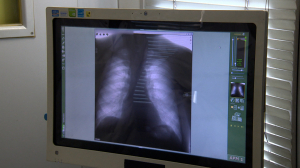

Стартовала неделя профилактики инфекционных заболеваний. Какова сейчас эпидобстановка в городе? Какие заболевания характерны для весенне-летнего сезона? Когда нужно делать прививку против клещевого энцефалита и насколько она эффективна? Чем опасен боррелиоз? Какова в Петербурге ситуация с туберкулёзом? И какие схемы лечения доказали свою эффективность?

Александр Пантелеев, главный внештатный специалист-фтизиатр Комитета по здравоохранению.